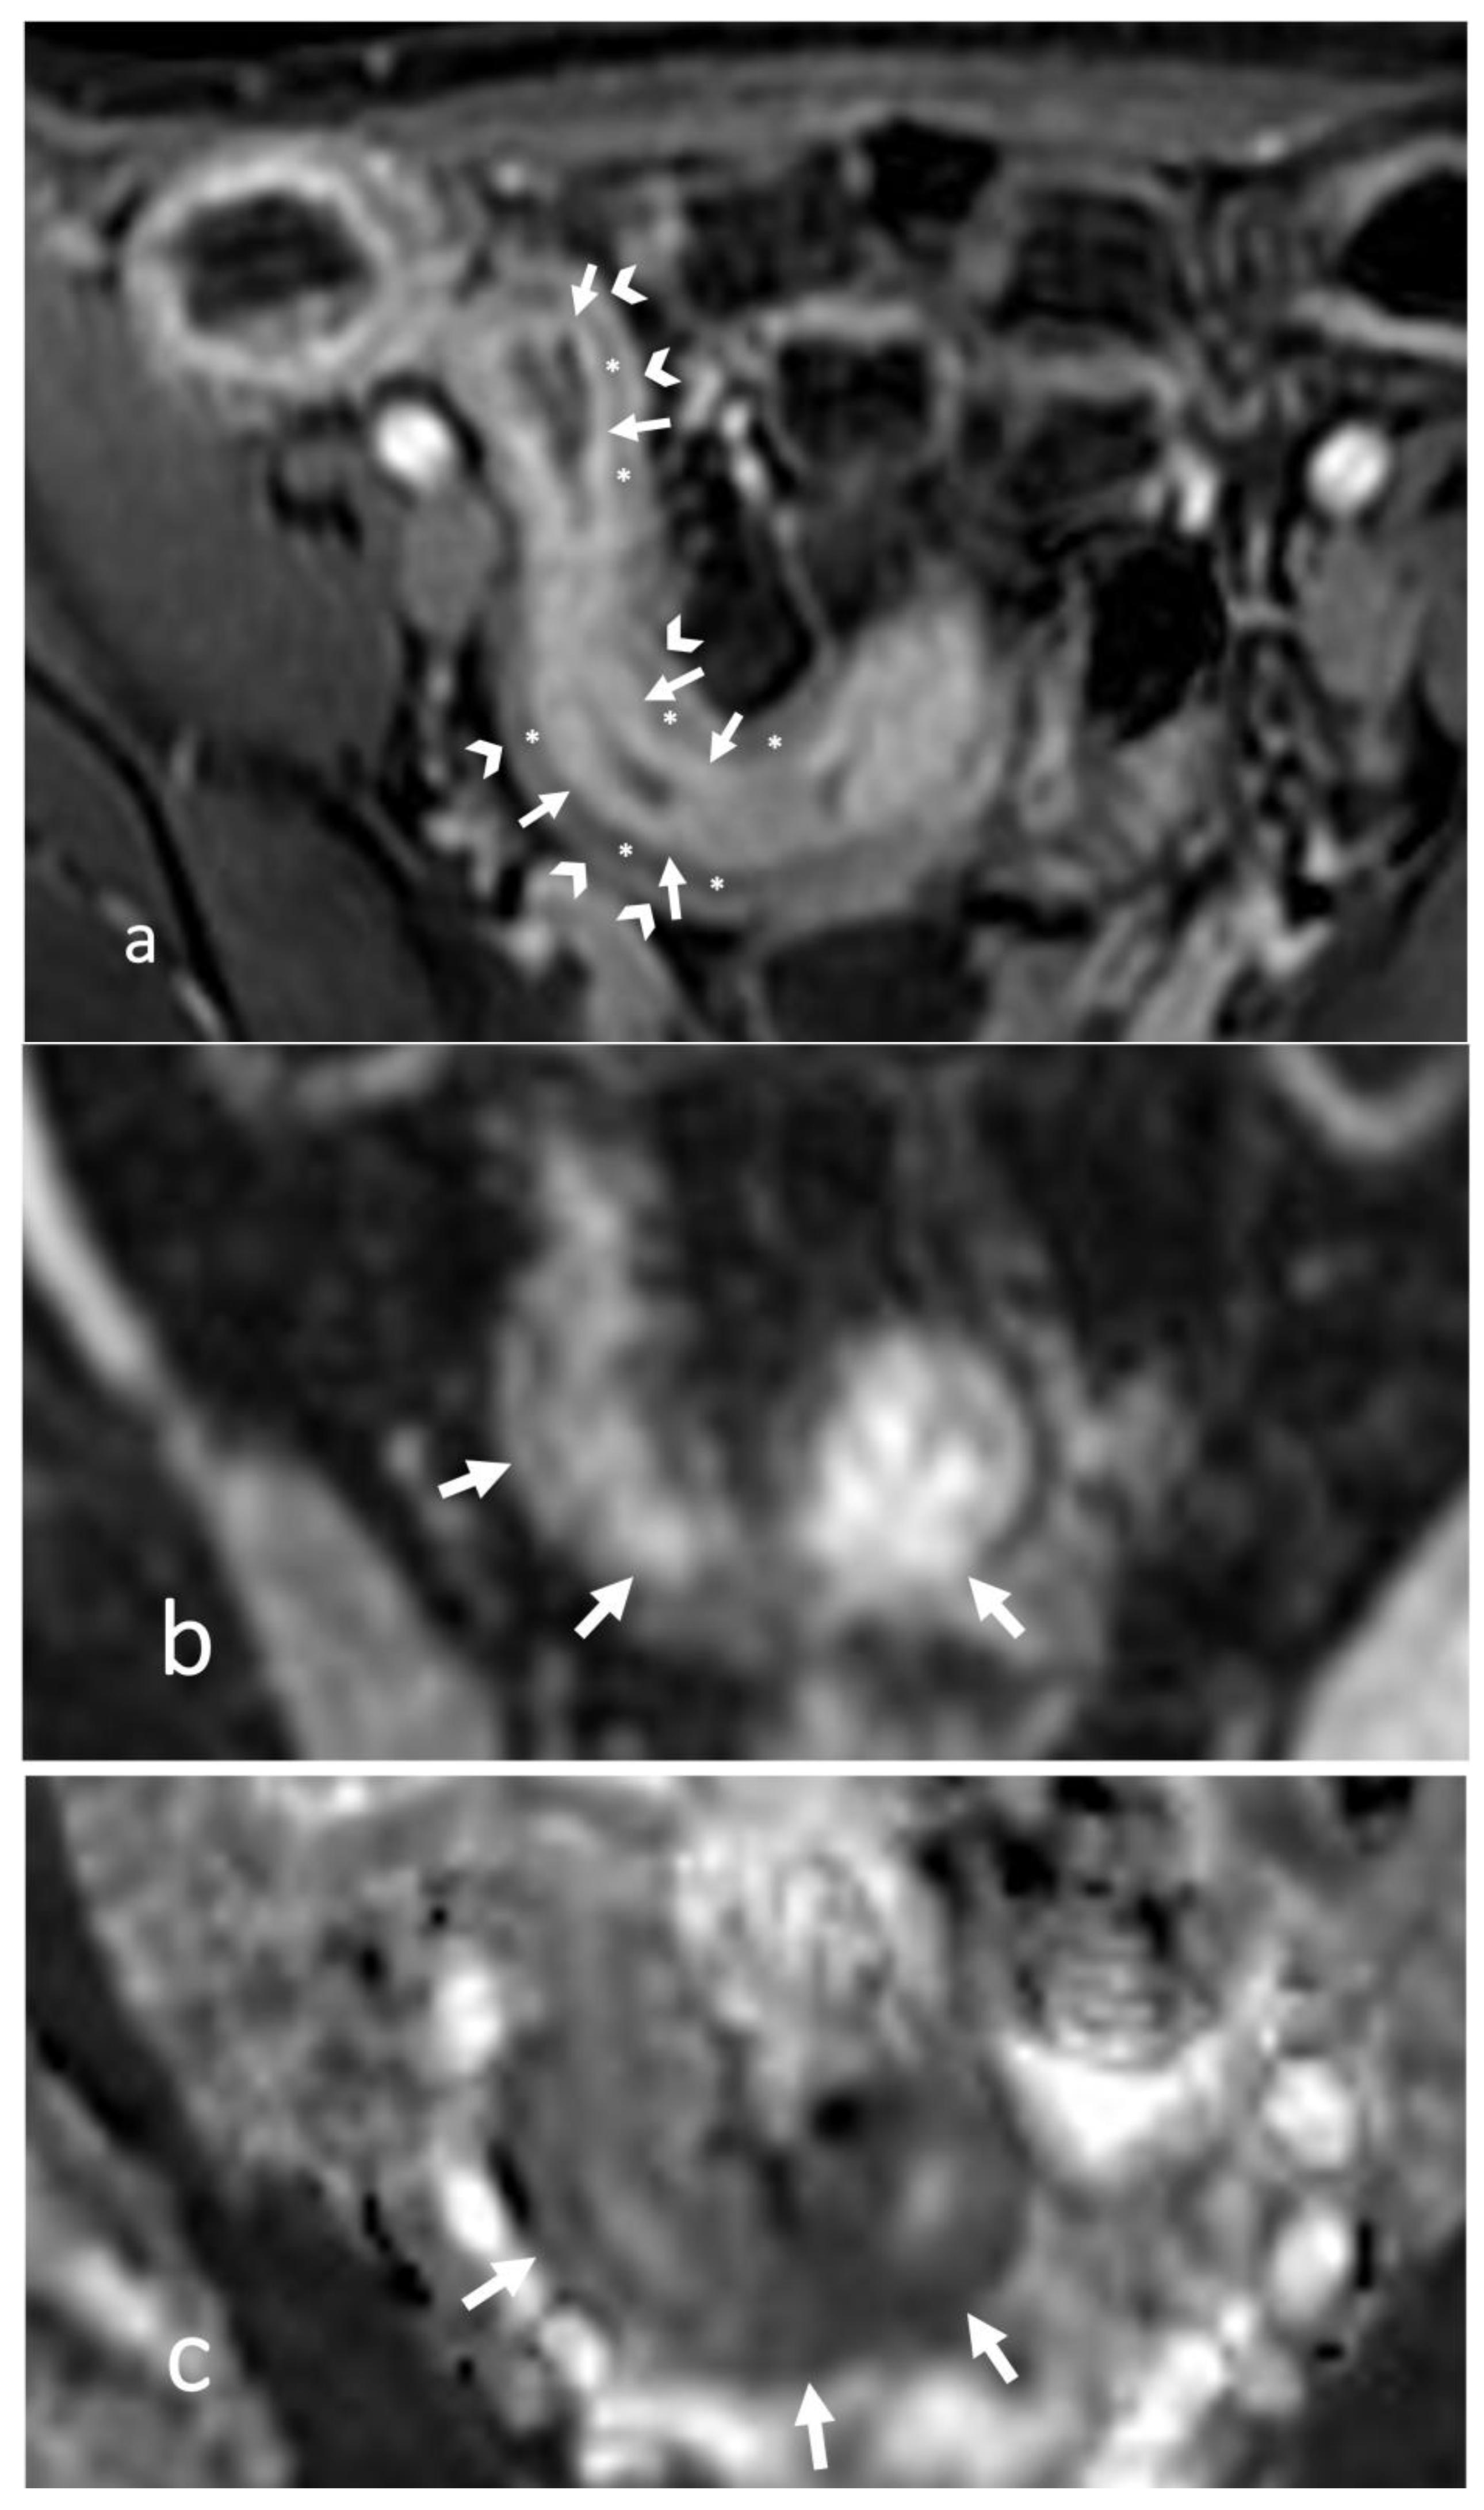

6. Is the Stricture Fibrotic or Inflammatory?